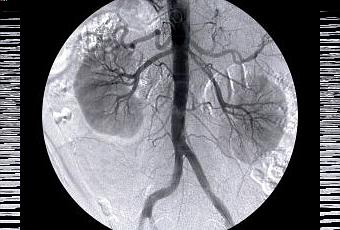

- de problèmes aux reins (insuffisance rénale) et aux yeux (lésions à la rétine pouvant mener à une perte de la vue) : encore une fois, en raison de la fragilisation des vaisseaux sanguins.